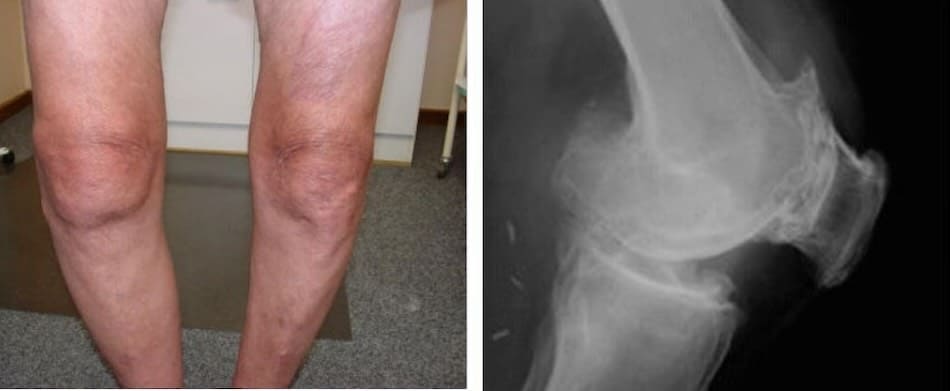

– Всеки един от тези хора е мислил, че „ще мине от само себе си“! Но ето докъде са стигнали: пълна загуба на подвижност, парализа, ампутация – доживотна зависимост от другите и ИНВАЛИДНА КОЛИЧКА! Повече от 90% от хората стават инвалиди само защото не са предприели правилните стъпки навреме. ИЗНОСВАНЕТО НА СТАВИТЕ С ВЪЗРАСТА ЧЕСТО ЗАПОЧВА БЕЗ НИКАКВА БОЛКА – като игнорирате първите симптоми, вие сами разрушавате живота си!

След като премина през десетки лекари, Мария Димитрова се обърна към д-р Венцислав Илиев и успя да победи болестта. През 2019 г. й бяха диагностицирани няколко увреждания на гръбначния стълб: междупрешленна херния, натиск върху нервите и деформация на прешлените. След две години настъпило внезапно влошаване на коленните стави, така че всяко движение стана мъчително. Тя нямаше близки роднини, но не се предаде и реши да се бори до край.

„Никога не съм си мислила, че ще остана неподвижна в собствения си дом – сама. Всичко започна с болки в долната част на гърба, но след две години състоянието се влоши: вече не можех да ходя. За осем месеца коленете ми напълно отказаха. Пълзех из къщата, куцайки, защото нямах пари за инвалидна количка, нито някой, който да ми помогне.

Когато ми предложиха операция, загубих надежда, че ще стъпя отново на краката си. Плаках през нощта, всичко изглеждаше като край... И тогава, слава Богу, успях да се свържа с д-р Венцислав Илиев, който ми изпрати препарат. След два месеца и половина бях отново на крака. Коленете ми станаха по-силни и болката в гърба изчезна!

- Всички тези снимки показват, че гелът „Reumax” възстановява здравето на ставите, дори в случаи, когато диагнозата изглеждаше като смълртна присъда. Без хирургични интервенции, без мъчителни болки, всички пациенти успяха да постигнат стабилно подобрение и да се върнат към нормалния си живот. ТОЗИ ГЕЛ НАПЪЛНО ПРОМЕНИ ХОДА НА ЛЕЧЕНИЕТО НА СТАВИТЕ И ГРЪБНАКА!